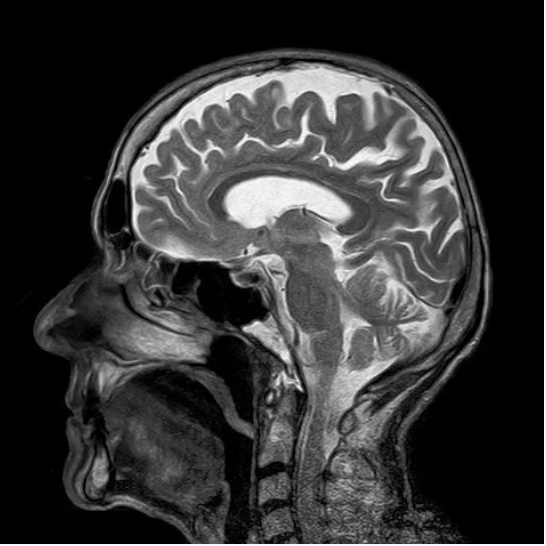

The next morning the patient returned to the medical center via ambulance after being disoriented at home. An MRI was performed which indicated signs of a recent stroke.